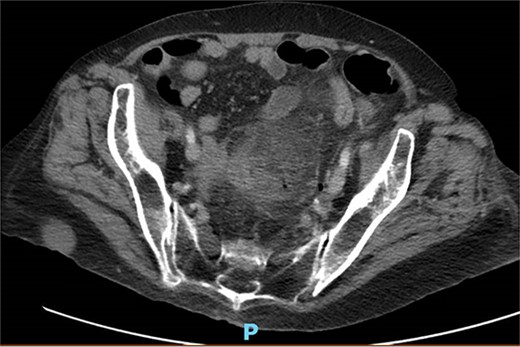

One month prior, the patient was admitted for complicated perforated sigmoid diverticulitis. Treatment included piperacillin-tazobactam (Zosyn), bowel rest, and fluid resuscitation. On hospital Day 6, her condition worsened with increased nausea, vomiting, and an elevated WBC count of 15. CT imaging revealed a 4.8 × 4.4 × 4.0 cm diverticular abscess, leading to CT-guided percutaneous drainage by interventional radiology (Figs 4–7). Cultures grew Citrobacter sedlakii and Enterococcus faecium vancomycin resistant Enteroccus (VRE), and treatment was adjusted to include Bactrim, followed by daptomycin and levofloxacin. The abscess resolved after 3 weeks, and the drain was removed before discharge. The patient was instructed to follow up with her surgeon and undergo a 6-week interval colonoscopy.

CT showing resolution of abscess with IR pigtail drain in place.